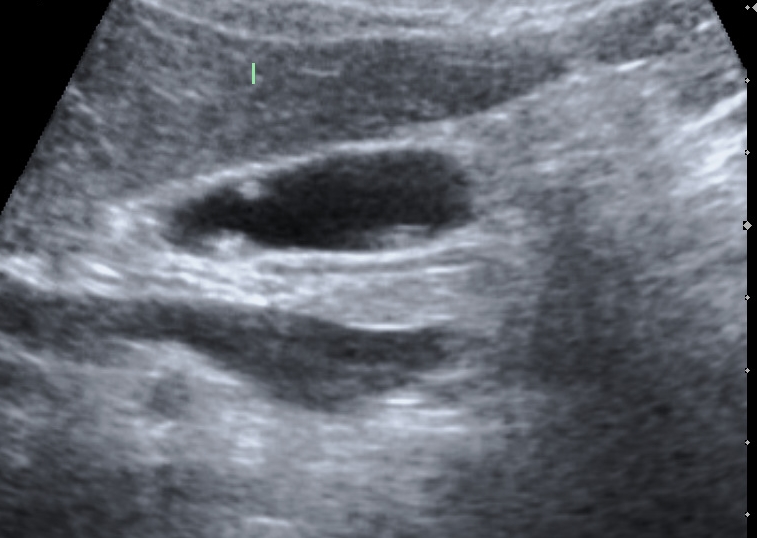

담낭 용종 진단하기

탐정이 수수께끼를 푸는 것처럼 의사도 담낭 용종이 있는지 알아낼 수 있는 방법이 있습니다.

의사는 초음파 기계와 같은 도구를 사용할 수 있는데, 이는 신체 내부를 사진으로 찍는 것과 같습니다. 이를 통해 담낭에 용종이 있는지 확인할 수 있습니다.